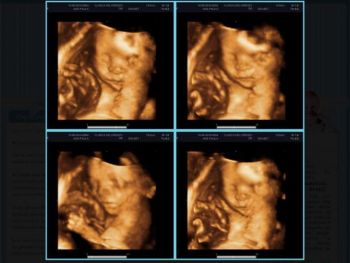

Grávida de quadrigêmeos teria copiado ultrassom de blogueira

Maria Verônica Aparecida Vieira, de 25 anos, que afirma estar grávida de quadrigêmeos, teria copiado as imagens dos bebês de um ultrassom postado na internet por uma blogueira que mora em Blumenau (SC).

Ana Paula Muckenberger, de 29 anos, mantém o blog desde o início da gestação de seu filho Pietro Rhuan, hoje com 1 ano e 4 meses. De acordo com ela, o ultrassom 3D apresentado no computador por Maria Verônica é de seu filho e foi feito quando ela estava grávida de 24 semanas. Foi publicado na internet em 15 de junho de 2010. "Recebi um e-mail alertando que a imagem apresentada na TV Record era a mesma do meu blog", diz.

Segundo Ana Paula, as quatro imagens apresentadas por Maria Verônica como sendo de suas quadrigêmeas na verdade são uma montagem feita por ela para estampar em seu blog.